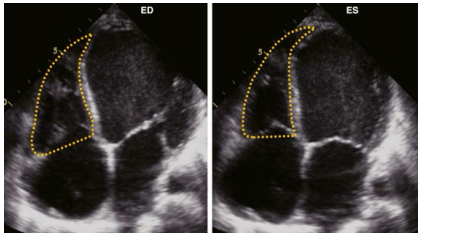

Fractional Area of Change, trace what border ? you want to start from where to the where and back to you started.

make measuremnet during what cardiac cycle ?

Trace the endocardial tissue border from the tricuspid annulus to apex back to the tricuspid annulus. Make measurement at both end diastole and end systole.

FAC reflects what?

what is the normal and abnormal %

FAC reflects both longitudinal and radial components of RV systolic contraction

Normal >35%

Abnormal < 35%

what is the FAC equation?

(RV ED Area- ES Area) / ED Area = FAC